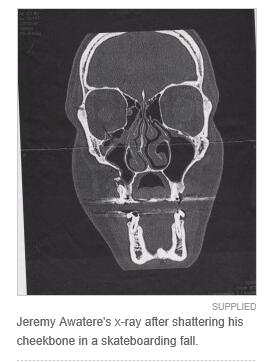

去年12月28日下午,23岁的Jeremy Awatere玩滑板时不慎摔倒,脸先着地,重重的摔在了Greymouth滑板公园的水泥地上。一个刚好路过的女人见状,赶紧帮忙把他送到了Grey Base Hospital的急诊部门。

“后来,医生终于来了,尽管我极力指出Jeremy的脸伤得有多么严重,”她说,“后来X光片也显示,Jeremy的脸确实骨折了,但医生却告诉我们这类骨折一般就是等待它自己愈合恢复,不过X光片会送到Christchurch Hospital再次确诊。”

直到一周后的1月4日,这对母子接到了从基督城医院打来的电话,询问他们最快什么时候可以到达基督城医院,“医院说希望安排Jeremy第二天一早就入院接受手术,因为一个专家在看了他的片子后认为他伤得非常严重,整个颧骨粉碎性骨折,至少需要安置3个固定板到他的脸上,”她说,“而且那名专家都不敢相信,过了这么长的时间,他居然没有发生感染,而且还没有剧烈的疼痛。”